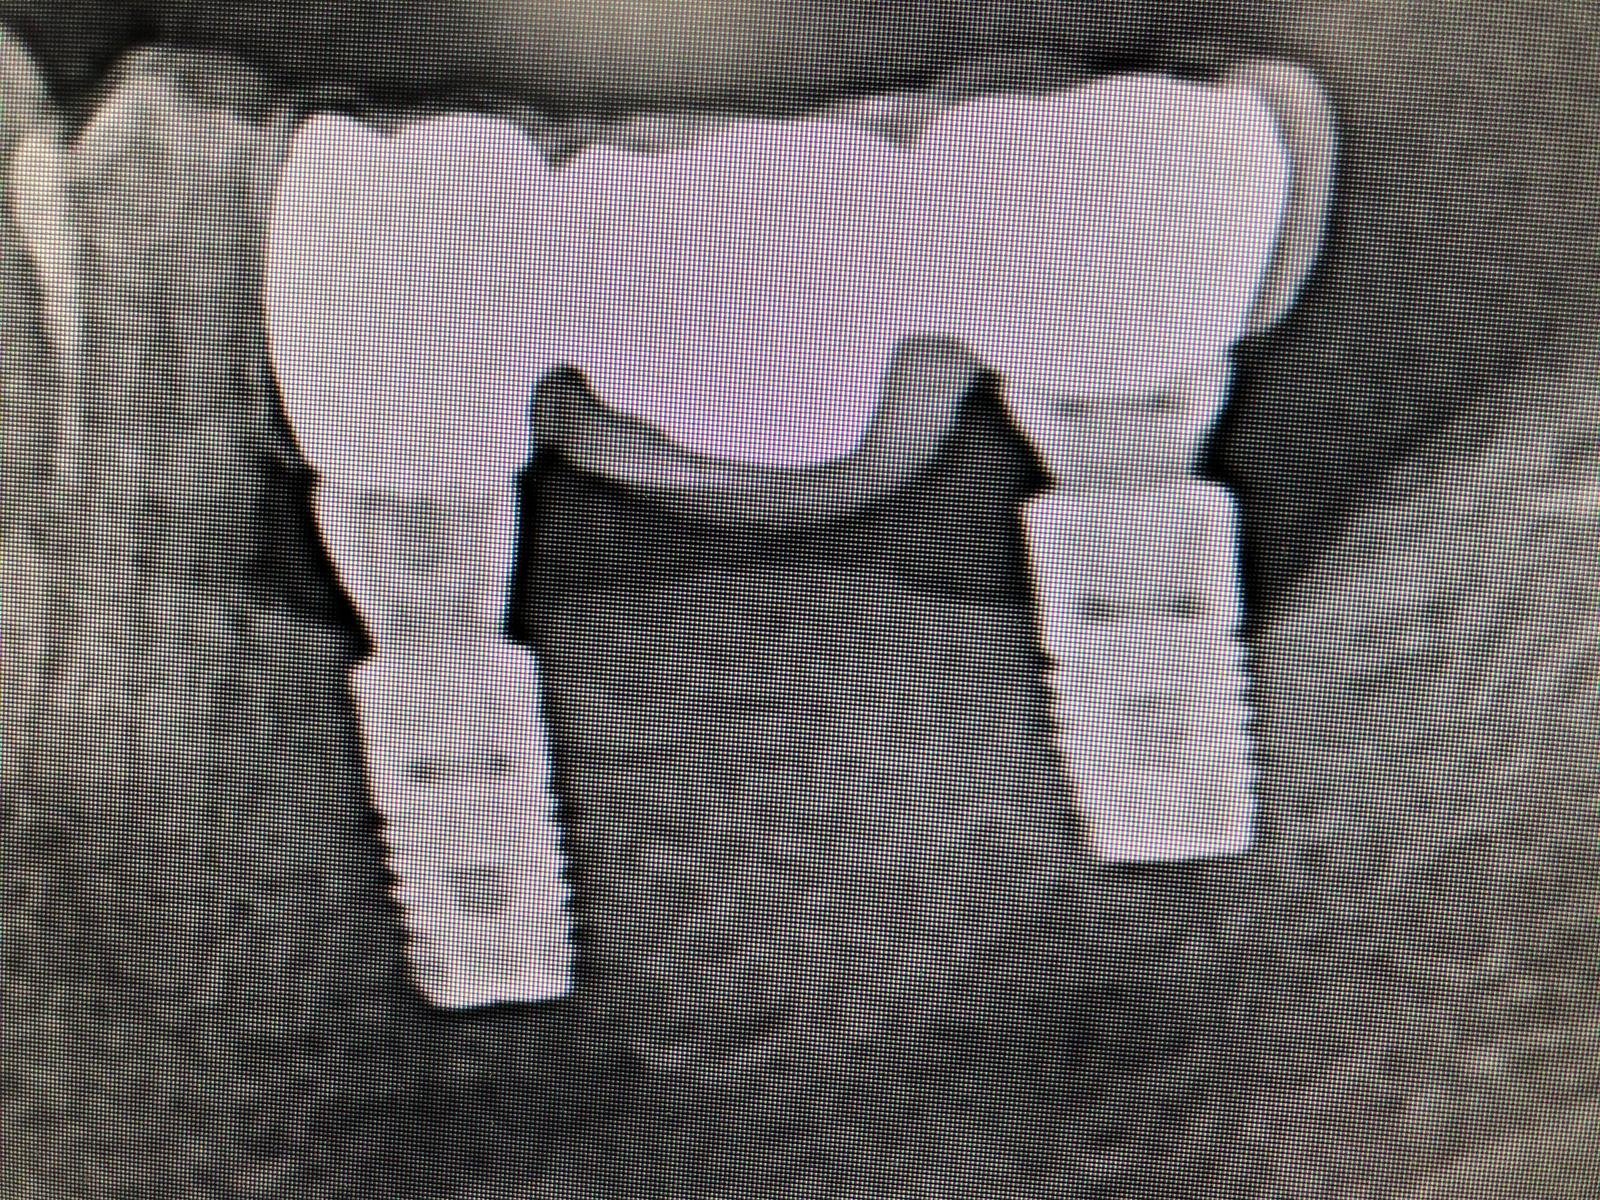

Hola, es un implante monobloque, que se ha colocado hacer 15 años, no es imbiodent. Alguien que sepa de qué casa comercial es?? Muchas gracias

buenas tardes. tengo este caso y necesito saber los aditamentos posibles compatibles. podrían echarme una mano? adjunto foto de la pegatina,pano y periapical un saludo y gracias